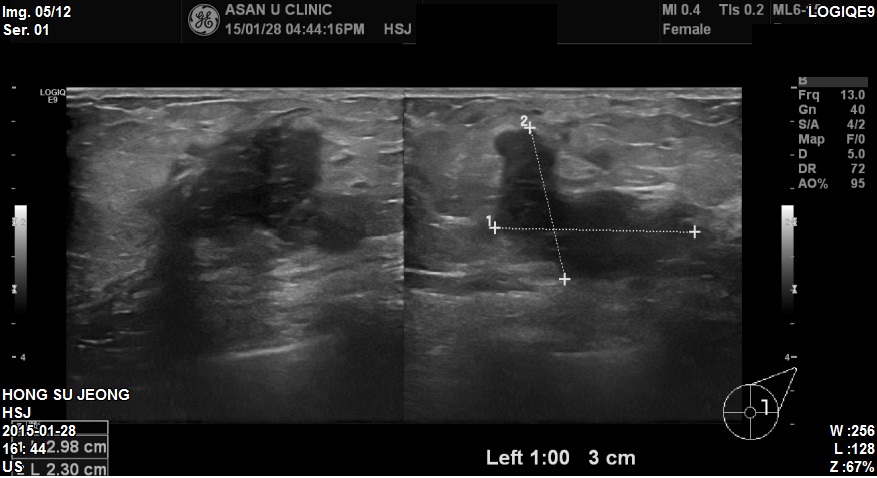

건진상 이상소견으로 내원하신 59세 환자분이십니다.

본원에서 좌측 1시방향에 2.9cm의 혹 조직검사하였고

침윤성유방암진단되었습니다.